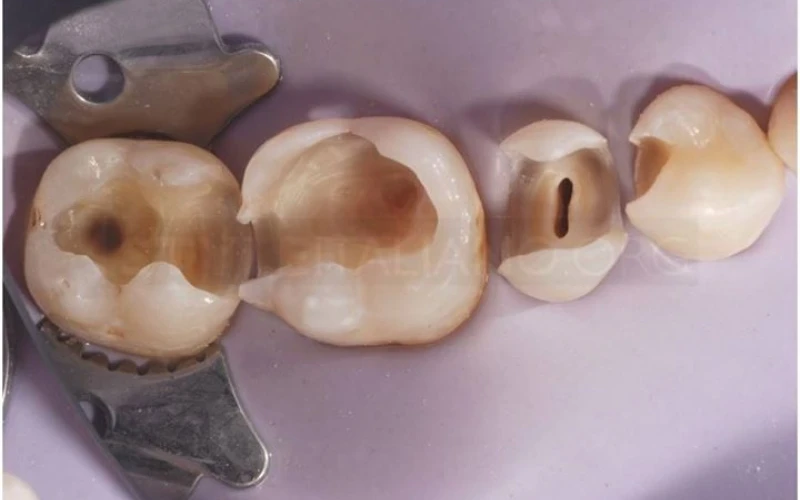

4. Xoang hàn đã được làm sạch. Đây là thời điểm tốt nhất để lựa chọn kế hoạch điều trị.

6. Đặt đê cao su và thực hiện điều trị tủy răng 4.5. Bắt đầu phục hình sơ bộ cho các răng.

11. Chụp phim X-quang sau khi tái tạo để đánh giá khoảng sinh học và độ dày của phục hình inlay.